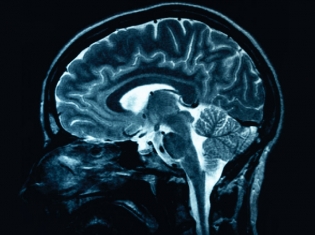

Schizophrenia is a mentally debilitating disorder characterized by delusions, disturbed thinking and lack of normal social behavior. At least half of them are not receiving appropriate care, and so finding clues that help identify the disorder could be vital.

“Our results not only open the door to a better understanding of schizophrenia,” Dr. Rouleau said, "they also give us valuable information about the molecular mechanisms involved in human brain development and function.”